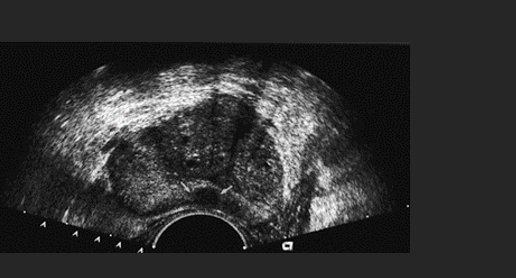

A patient presents with a history of hematuria and elevated prostate specific antigen(PSA). The neoplasm identified by the arrows is located in which region of the prostate gland? –

D. Peripheral zone